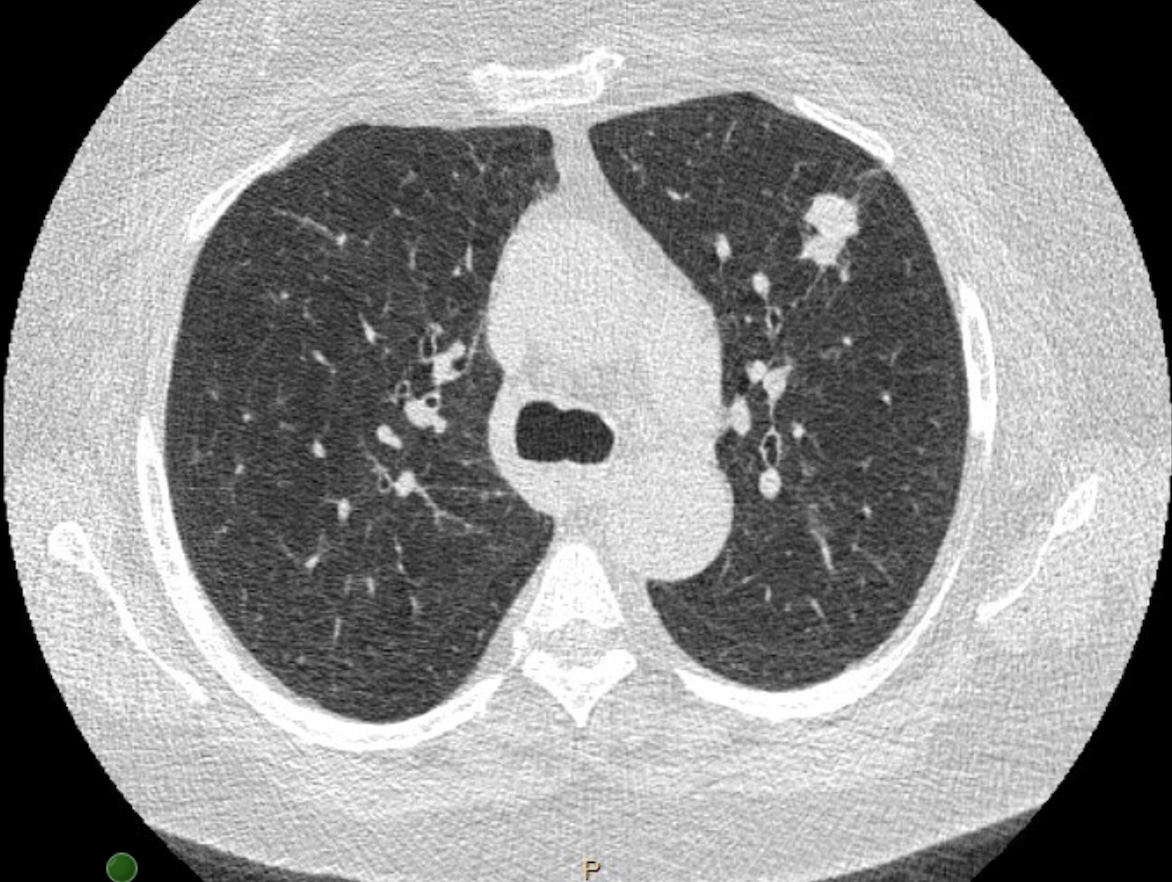

A multicenter prospective study of robotic-assisted bronchoscopy shows that RAB-guided sampling of peripheral pulmonary lesions compares favorably with results from sizable nonrobotic #bronchoscopy studies.

Read more in the August #JournalCHEST issue: hubs.la/Q03Cql920